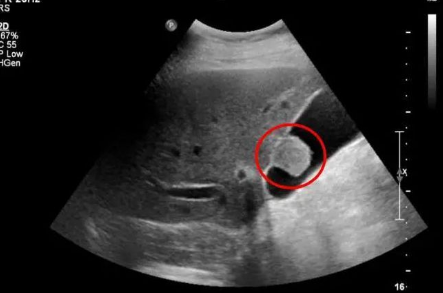

胆囊息肉患者大部分都是想要保住胆囊的 , 但无奈除了定期复查及保胆取息外 , 大多数医院并没有给到他们更好的治疗方法 。 并且保胆取息手术的风险还很大 , 术后也不能达到患者想要的效果 。

“保胆”手术除开手术时的风险 , 及手术对患者身体影响 。 虽然看起来已经保住了胆囊 , 但胆囊也会存在息肉复发、胆囊收缩功能障碍、癌变风险等隐患 。 因此可得保胆取息表面上是保住了胆囊 , 但依旧会对患者带来新的隐患 。

“保胆”术后胆囊息肉复发的主要原因是“术中遗留和残留息肉” , 也就是没有取净 , 这就不是息肉复发的问题了 , 而是手术失败;即使所谓“新式保胆取息”手术是在胆道镜下直视将息肉取净 , 但引发息肉的病灶不除 , 胆囊息肉依然会再次出现 , 到头来还是得切除胆囊 。